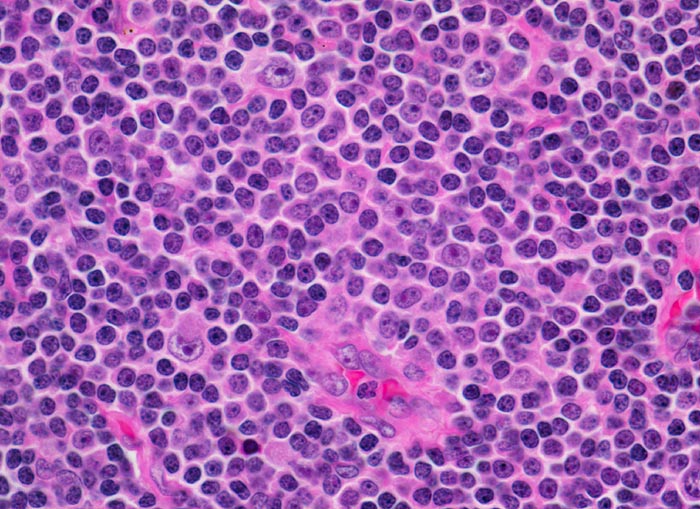

Befallene Lymphknoten weisen eine Zerstörung der normalen Architektur auf. Die neoplastischen Zellen bilden auf einem dunklen Hintergrund kleiner Zellen heller erscheinende Pseudofollikel bestehend aus vermehrt Paraimmunoblasten. Der dominierende Zelltyp ist etwas grösser als ein normaler Lymphozyt, der Kern ist rund und das Chromatin verklumpt. Der Zytoplasmasaum ist sehr schmal.

Morphologische Merkmale:

• Vergrösserter Lymphknoten mit zerstörter Lymphknotenarchitektur.

• Diffuse Infiltration des Lymphknotens durch monomorphe kleinlymphozytische Lymphomzellen.

• Unscharf begrenzte helle Areale (Proliferationszentren) auf dunkelblauem Hintergrund.

• Proliferationszentren (=Pseudofollikel) bestehend aus Lymphozyten und Paraimmunoblasten.